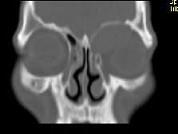

问题 男,53岁,近两年来渐进性头痛,伴左眼球外突,并向前下方移位,CT检查如图,最可能诊断为 ( )

选项 A、眶内炎性假瘤 B、眼格氏病 C、左额窦癌 D、左额窦黏液囊肿 E、额窦炎症

答案 D